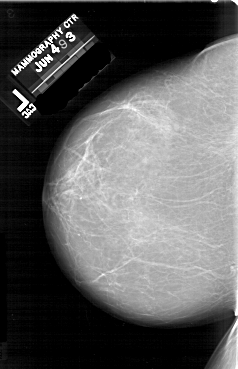

A_1640_1.LEFT_MLO

A_1640_1.LEFT_CC

LEFT_CC LINES 6631 PIXELS_PER_LINE 4276 BITS_PER_PIXEL 12 RESOLUTION 43.5 NON_OVERLAY

LEFT_MLO LINES 6421 PIXELS_PER_LINE 3991 BITS_PER_PIXEL 12 RESOLUTION 43.5 NON_OVERLAY